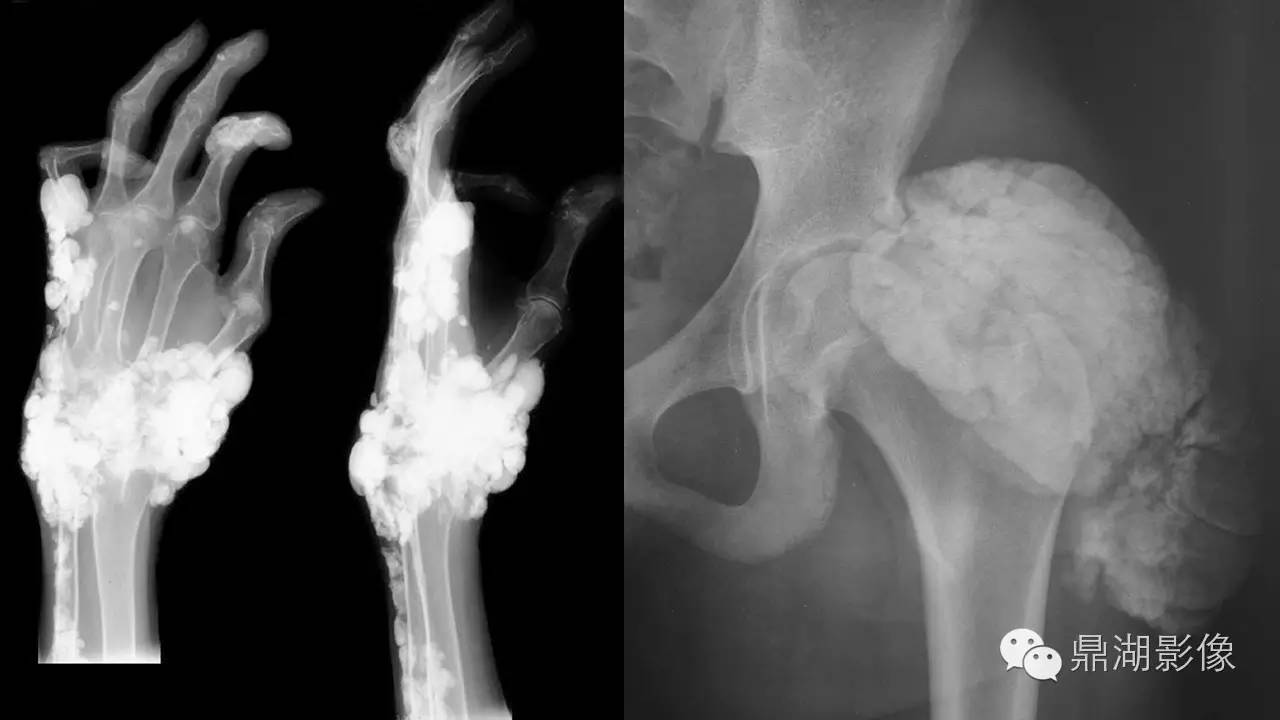

软组织钙化(的鉴别)